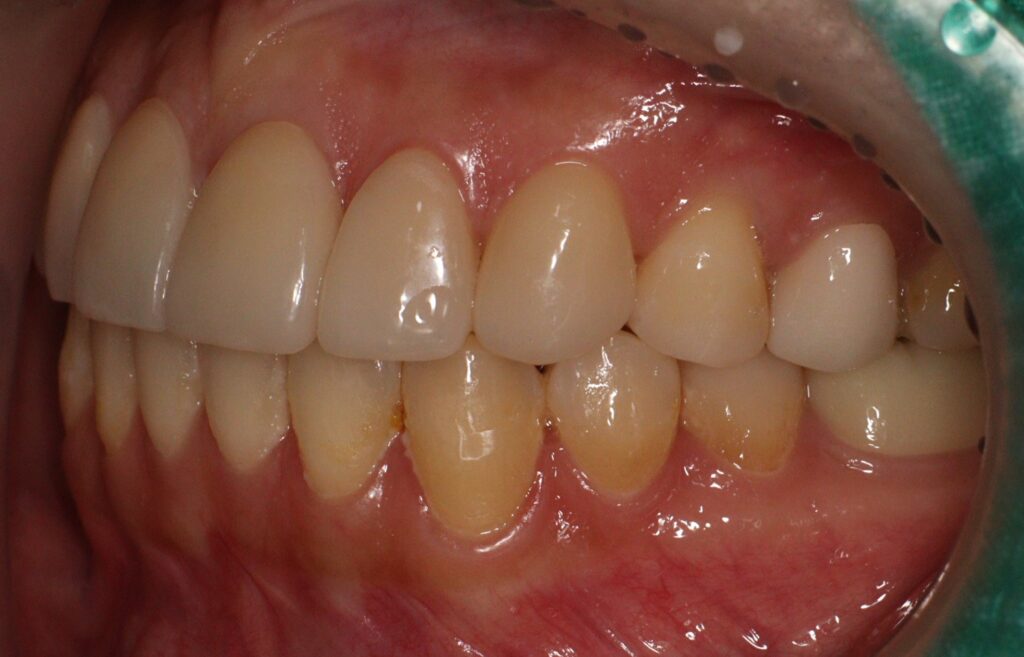

이어서 나머지 치아에서는 치경부 우식 부위를

중심으로 복합레진 수복을 시행하여

손상된 부위를 보존하고 추가적인 진행을 방지하였습니다.

또한 우식 범위가 넓거나 교합 부담이

큰 부위에는 인레이 치료를 적용하여

내구성을 확보하였고,

치수까지 영향을 받은 치아에 대해서는

근관치료를 선행한 후 크라운으로

최종 수복을 진행하였습니다.